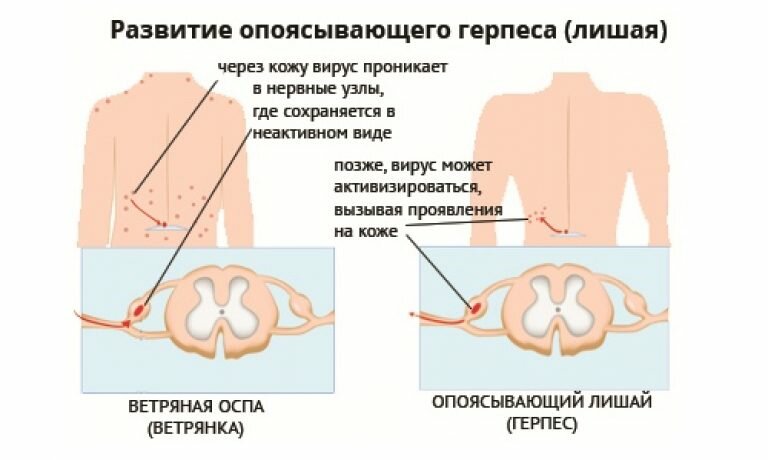

Опоясывающий лишай – вирусное заболевание при котором возникает болезненная сыпь на к Далее...